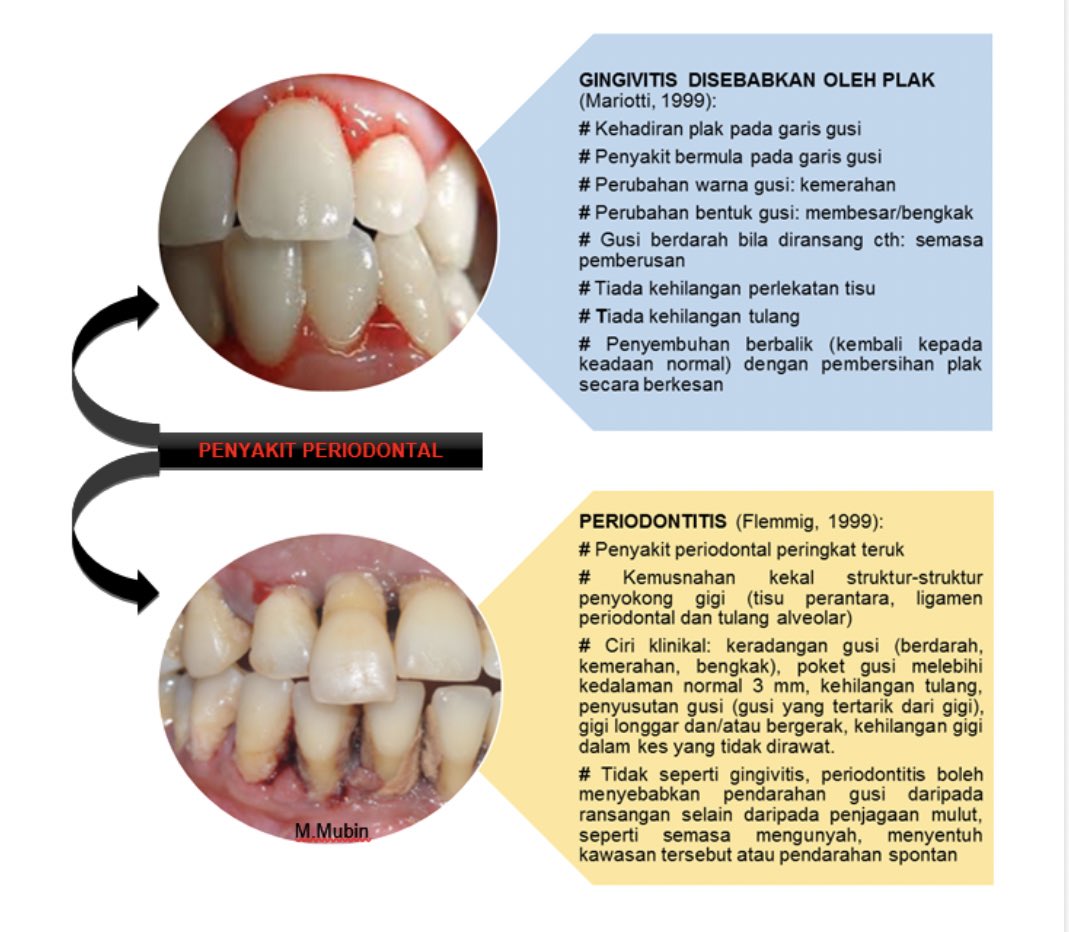

Pastinya sekiranya masalah itu tidak dirawat ia mungkin berkembang menjadi penyakit gusi lebih serius yang dipanggil periodontitis.

PENYAKIT periodontal atau gusi biasanya disebabkan oleh bakteria plak yang berada di sepanjang garisan gusi dan telah menjejaskan 144 juta atau 94 peratus rakyat Malaysia. Gusi berdarah tidak cuma terjadi akibat masalah kesehatan pada gigi dan mulut. Gusi berdarah adalah salah satu isyarat gingivitis.

Apabila plak dan kaviti menyebabkan bakteria terkumpul pada bahagian gigi gusi anda gingiva mungkin berhadapan dengan masalah keradangan. Gingivitis yang tidak ditangani juga dapat menyebabkan. Ia boleh jadi disebabkan oleh sejenis virus dikenali sebagai herpes simplex-1 HSV1.

Gusi dapat mengalami beberapa masalah seperti salah satunya yaitu keluarnya darah dari gusi baik itu secara tiba-tiba ataupun merupakan akibat dari permukaan gusi yang terluka sehingga membuat pembuluh darah yang ada di bawahnya pecah dan mengeluarkan darah. Penyakit gusi ini berlaku disebabkan oleh plak di sempadan gusi. Jadi pastikan asupan nutrisi vitamin C dari makanan seperti brokoli strawberry jeruk dll dan asupan nutrisi vitamin K dari makanan seperti bayam kale kacang kedelai.

Gusi sering berdarah tiba-tiba adakalanya dapat menimbulkan kepanikan tersendiri karena dapat terjadi secara tiba-tiba tanpa mengetahui apa penyebab sampai gusi dapat berdarah. Gingivitis ialah keradangan yang berlaku pada gusi. Keadaan ini boleh juga menyebabkan gusi berdarah.

Wani On Twitter 1 Penyakit Gusi Periodontal Ini Antara Penyebab Yang Paling Kerap Yang Menyumbang Kepada Gusi Berdarah Penyakit Gusi Yang Paling Common Berlaku Ialah Gingivitis Dan Periodontitis Apa Benda Gingivitis Dan Periodontits